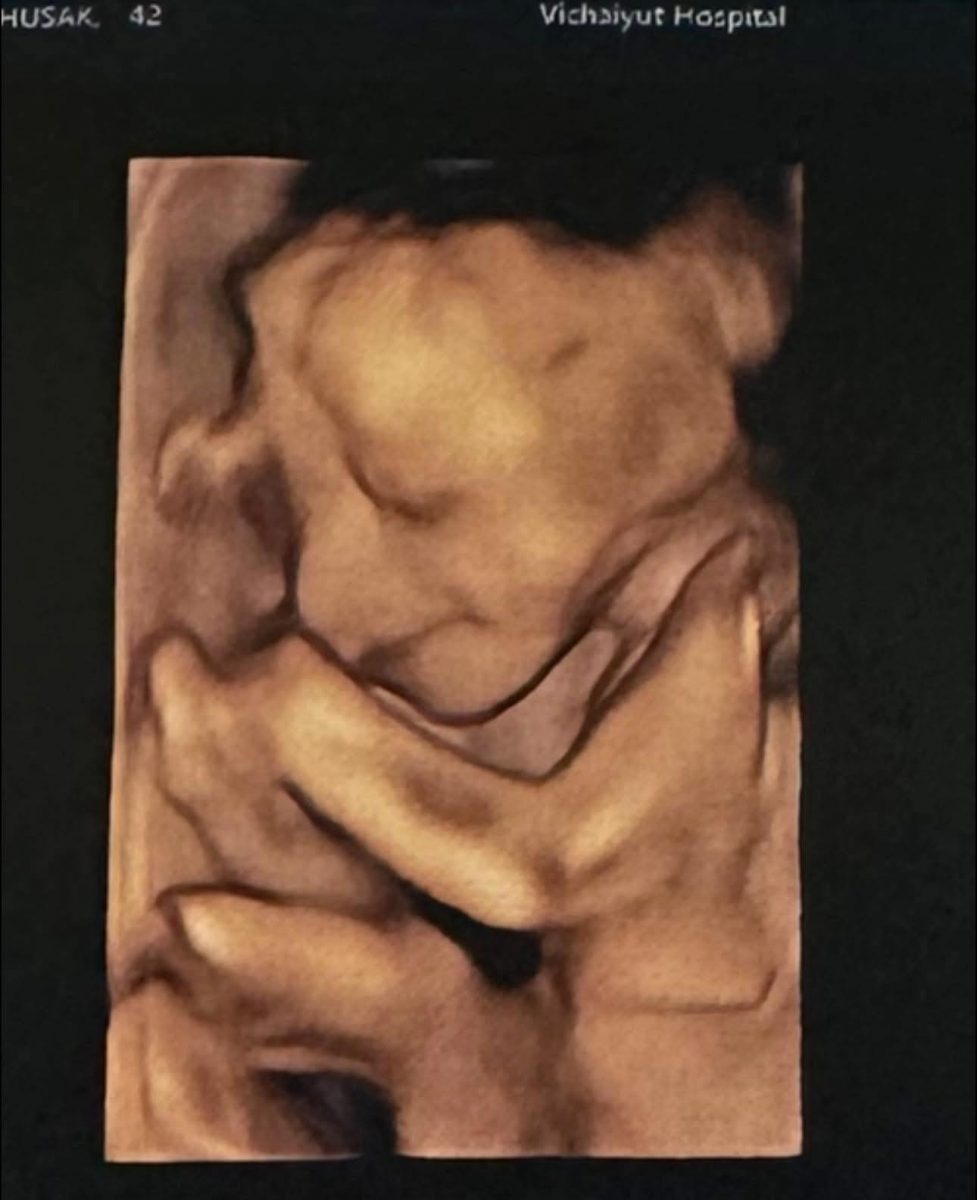

จากภาพอัลตราซาวด์เผยให้เห็นเค้าโครงใบหน้าของ น้องมีเมตตา อย่างชัดเจน นอนยิ้มหวานละมุน แถมจมูกโด่งสะดุดตา เรียกได้ว่าน่ารักน่าชังตั้งแต่อยู่ในท้อง โดย พ่อเจมส์ เขียนแคปชันด้วยความเอ็นดูว่า “แม่หนูมีเมตตาของฉัน จมูกโด่ง ยิ้มหวาน” พร้อมอัปเดตว่า คุณหมอกล้วย แพทย์ผู้ดูแลครรภ์ครูก้อย ยืนยันว่าลูกน้อยแข็งแรงสมบูรณ์ พัฒนาการเป็นไปตามเกณฑ์ทุกด้าน ก่อนจะปิดท้ายด้วยมุกขำ ๆ สไตล์คุณพ่อว่า “สินค้าเด็กเข้าได้เลยครับ ( ฮาาา…. )” ทำเอาแฟน ๆ เข้ามากดไลก์และคอมเมนต์ชื่นชมความน่ารักของ น้องมีเมตตา อย่างล้นหลาม

ด้านคุณแม่คนสวย ครูก้อย นัชชา ก็ไม่น้อยหน้า โพสต์คลิปอัลตราซาวด์ของลูกสาวเช่นกัน พร้อมแคปชันสั้น ๆ ว่า “แม่ว่า…ดูทรงยาว ทรงคมนะ” งานนี้หลายคนอดเดาไม่ได้ว่า น้องมีเมตตาน่าจะได้ความสูงยาวและเค้าโครงคม ๆ มาจากพ่อเจมส์และแม่ก้อยแบบเต็ม ๆ

ก่อนหน้านี้ ครูก้อยเคยให้สัมภาษณ์ว่า การตั้งครรภ์ครั้งนี้แพ้ท้องน้อยมาก อารมณ์ดี มีความสุขตลอด เนื่องจากมีการเตรียมความพร้อมอย่างรอบด้านตั้งแต่ก่อนตั้งครรภ์ ทั้งการจัดการเรื่องงาน โภชนาการ และการออกกำลังกาย เนื่องจากมีภาวะมีบุตรยากจึงมีความเตรียมความพร้อมเป็นพิเศษ เมื่อทุกอย่างลงตัวก็ส่งผลให้ลูกน้อยในท้องอารมณ์ดีตามไปด้วย จนเห็นได้จากภาพอัลตราซาวด์ที่น้องมีเมตตานอนยิ้มหวาน น่าเอ็นดูตั้งแต่อยู่ในท้อง